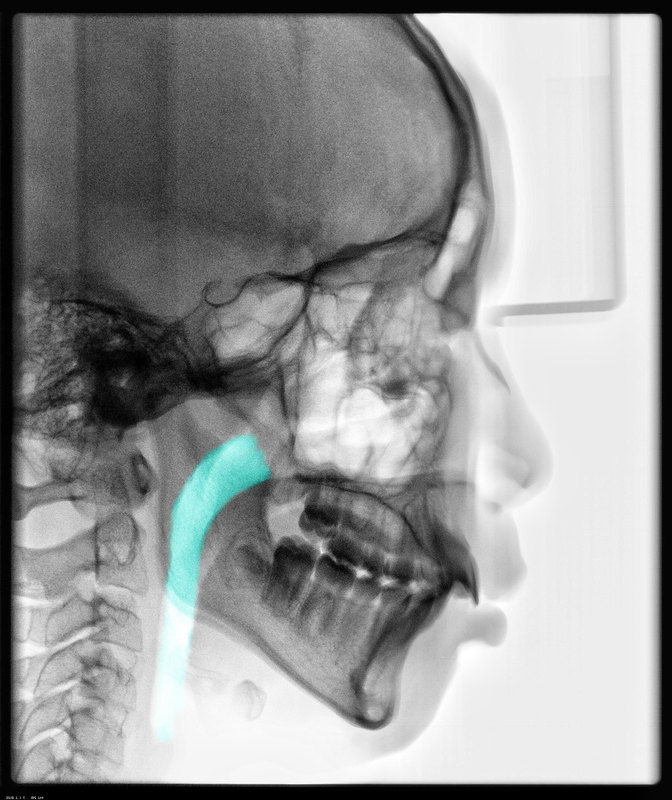

近幾年來兒童的腺樣體肥大已經成為一個網紅的問題,在腺樣體肥大的治療上存在很多誤區(qū)和過度的醫(yī)療。只要一發(fā)現(xiàn)腺樣體肥大,就會被要求去接受手術治療,那么是否只要一發(fā)現(xiàn)腺樣體就必須手術,是否手術后就能解決所有問題?誤區(qū)一:只要在鼻咽部發(fā)現(xiàn)腺樣體就被認為有腺樣體肥大,不正確。腺樣體本質是淋巴組織,是我們咽部淋巴環(huán)的一部分,兒童時期只要去檢查都會發(fā)現(xiàn)有增生,肥大。在青春發(fā)育期以后會慢慢逐步萎縮。誤區(qū)二,有部分孩子是因為鼻塞,流涕,咳嗽去就診,發(fā)現(xiàn)腺樣體肥大,被要求手術治療,有幫助嗎?沒有,答案是否定的。有部分孩子是因為咽部不適,經常吸鼻,清嗓子去就診,也被要求手術,有幫助嗎?同樣沒有。只有當兒童的慢性鼻竇炎經過正規(guī)的2-3個月藥物治療沒有好轉,并引發(fā)分泌性中耳炎時,才需要手術治療。誤區(qū)三,有部分孩子存在口呼吸的情況,特別是一些8歲以上的孩子,這些孩子的口呼吸是口腔牙合面問題導致,比如小下頜,下頜后縮,上牙前突等,而他們的腺樣體僅僅輕度增生,或已經開始萎縮,這個時候只要進行咬合誘導,口肌功能訓練就可以完全解決問題。這點輕度增生的腺樣體完全不影響整個氣道的通暢程度,這個時候去手術就是過度治療,完全沒有必要去吃這個苦頭,不手術也不會影響口腔干預的效果。如圖這個孩子,藍色部分顯示他的氣道從上至下是基本通暢的,完全不用再手術,進行下頜前導就可以。上圖是一個來就診口呼吸的8歲女孩,紅色部分腺樣體是略有增生,完全沒有必要手術,藍色顯示氣道,通暢,上牙前突,與父母遺傳因素有關,導致口呼吸,直接在兒童口腔醫(yī)生處治療就可以,避免一次不必要的全麻手術。所以家長在決定手術前,一定要慎重,多咨詢醫(yī)生,最后再做決定。誤區(qū)四,兒童腺樣體手術在哪里做?現(xiàn)在有一些兒外醫(yī)生,口腔醫(yī)生也開始涉足腺樣體手術。但是腺樣體手術最難處理的是鼻咽部后鼻孔區(qū),如果處理不當,一容易造成后鼻孔區(qū)腺樣體殘留,咽鼓管扁桃體殘留增生,影響手術后效果。二是后鼻孔區(qū)如果處理不當,損傷,會形成后鼻孔狹窄,閉鎖,影響手術后通氣功能,甚至影響咽鼓管功能,導致永久性聽力影響。所以我們耳鼻咽喉的??漆t(yī)生是在鼻內窺鏡下操作,完全避免這方面的損傷。所以手術請選擇在耳鼻喉科進行為佳。最后,腺樣體是否手術是有診斷和治療指南的,目前我們遵循2021版的中國兒童OSAS指南來進行臨床診斷和治療。